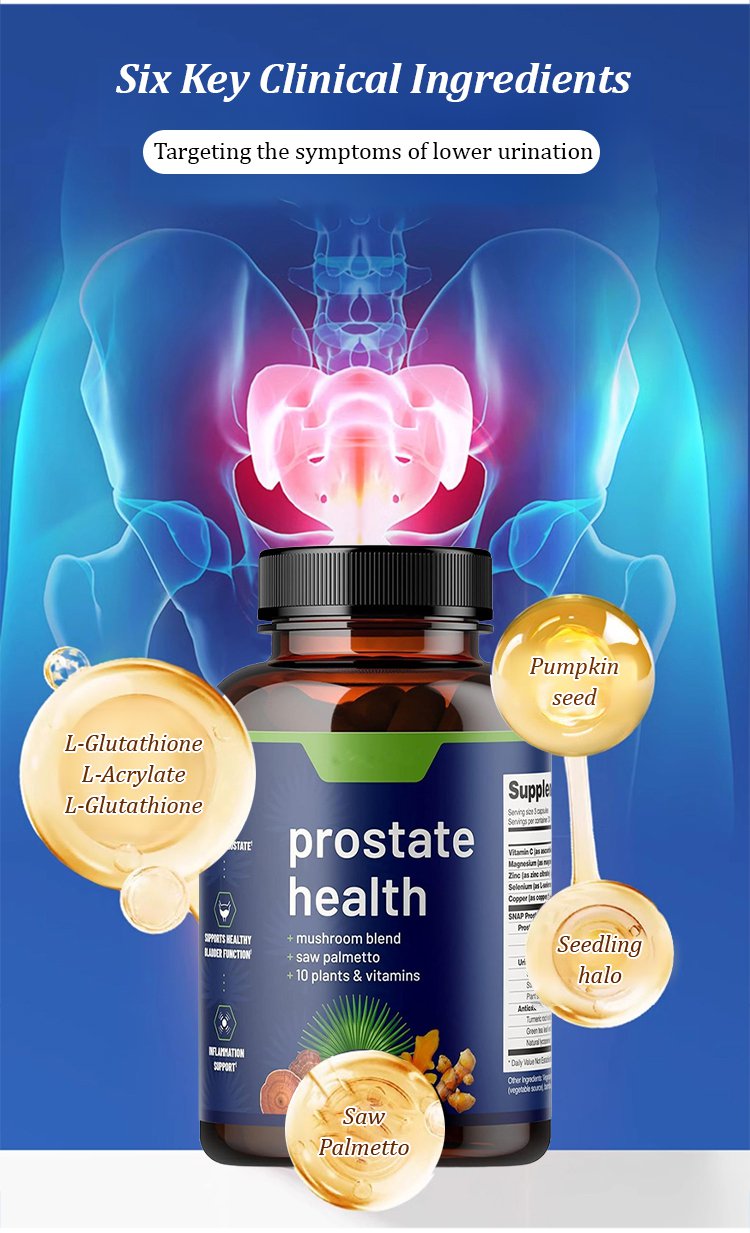

Lancetswell™ Saw Palmetto Prostate Health Supplement are meticulously crafted to provide comprehensive support for prostate health and alleviate the bothersome symptoms often associated with prostate issues.

Reducing Inflammation: Prostate problems are frequently linked to inflammation within the prostate gland. The capsules contain a unique blend of natural compounds renowned for their potent anti-inflammatory properties. By targeting and reducing inflammation in the prostate, these capsules help alleviate pain, discomfort, and swelling associated with prostate issues. Interferes with the production or activity of inflammatory mediators, such as cytokines and prostaglandins. By doing so, they help modulate the inflammatory response, resulting in a decrease in inflammation and swelling.

Enhancing Urinary Function: Frequent nighttime urination is a common symptom experienced by individuals with prostate issues. Lancetswell™ Prostate Health Capsules specifically target the smooth muscles and tissues surrounding the prostate and bladder. Through their action, these Capsules relax and strengthen these structures, leading to improved bladder control, reduced urinary urgency, and a healthier urinary flow. This ultimately results in fewer nighttime trips to the bathroom.